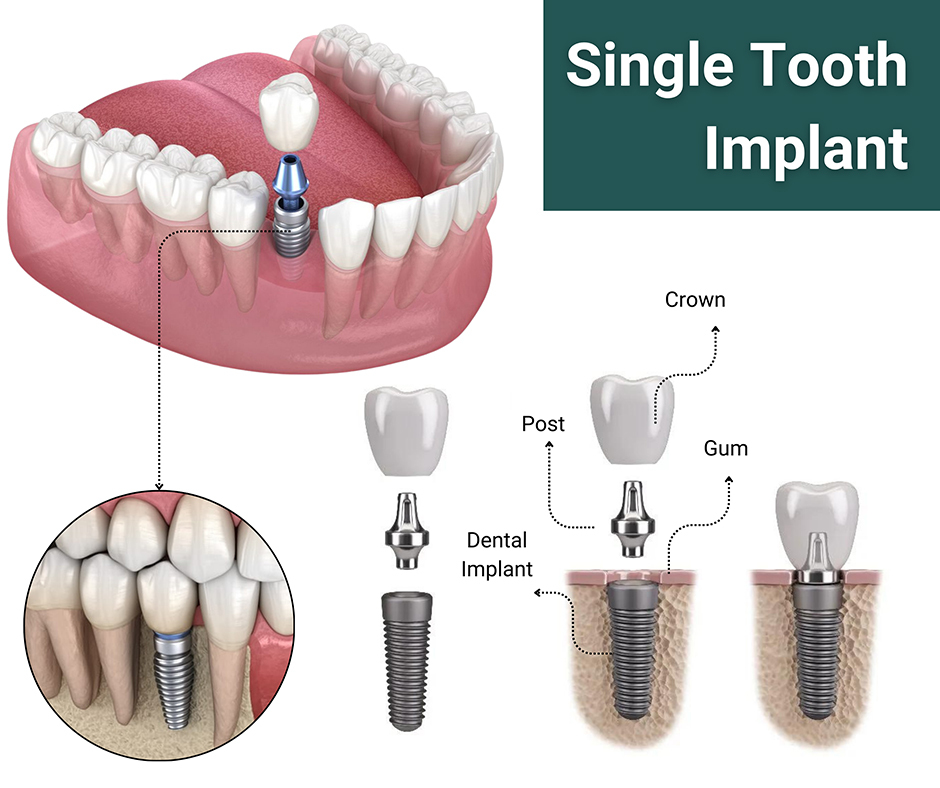

Early-stage gum disease (gingivitis) can often be managed with a professional cleaning and improved home care. More advanced disease may require scaling and root planing, surgical pocket reduction, or regenerative procedures. The sooner you come in, the more options are available — and the more of your natural teeth we can preserve.